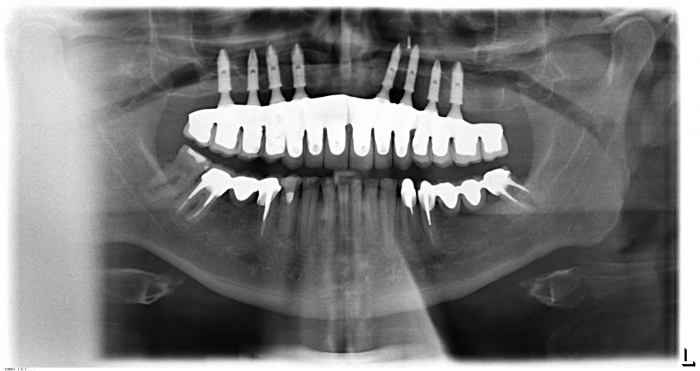

Raio X com prótese em porcelana com dentes individuais instalada - Clínica Cliniface

Raio X com prótese em porcelana com dentes individuais instalada